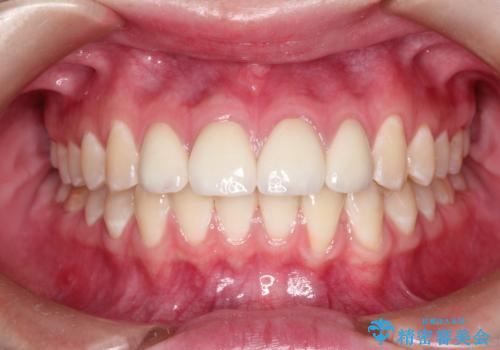

ご自身の歯を削る必要がありましたが、セラミッククラウンを装着することで、審美的改善ができました。

まだらな色の前歯をきれいにしたい セラミック治療による見た目の改善